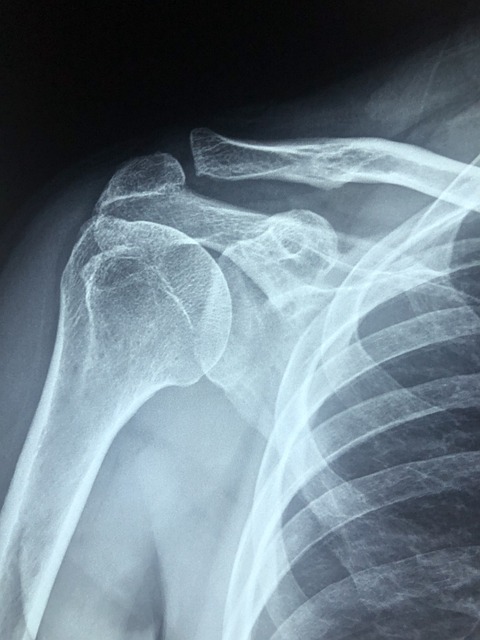

1-5. 어깨 관절염

퇴행성 변화 또는 류마티스성 관절염에 의해 관절 연골이 마모되면서 통증이 유발됩니다. 어깨가 뻣뻣하고, 움직일 때 소리가 나는 경우 의심해볼 수 있습니다.